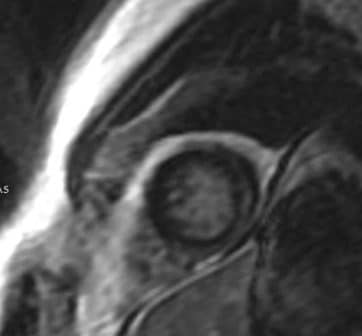

- 2. Imagerie par résonance magnétique (IRM)